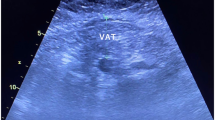

Computed tomography coronary angiography (CTCA) provides a non-invasive method to evaluate coronary artery disease that allows the phenotyping of atherosclerotic plaques and surrounding perivascular adipose tissue (PVAT).

Bidirectional signalling between the coronary arteries and the adjacent PVAT might contribute to the progression of atherosclerosis.

Qi, X.-Y. et al. Perivascular adipose tissue (PVAT) in atherosclerosis: a double-edged sword. Cardiovasc. Diabetol. 17, 134 (2018).

Tan, N., Dey, D., Marwick, T. H. & Nerlekar, N. Pericoronary adipose tissue as a marker of cardiovascular risk. J. Am. Coll. Cardiol. 81, 913–923 (2023).